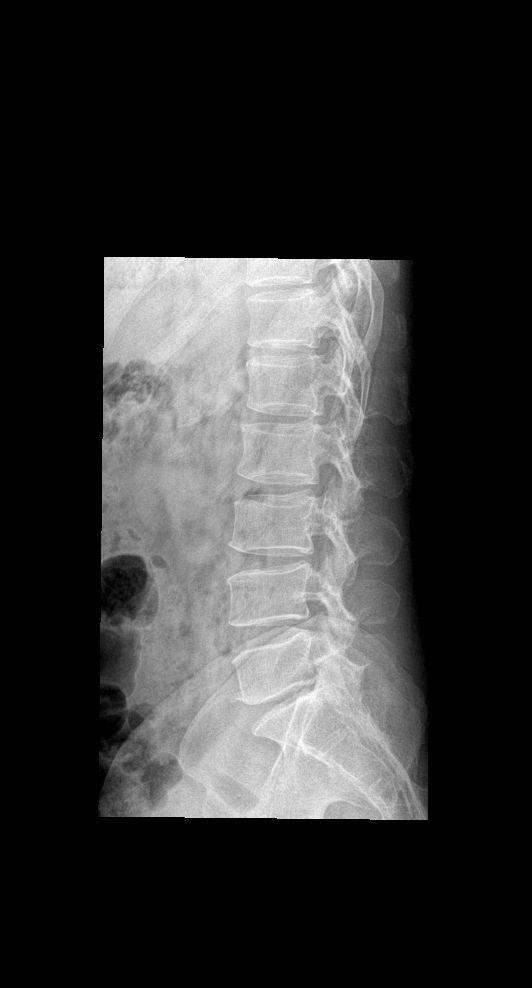

男34 腰椎疼痛 颈椎正侧+腰椎正侧